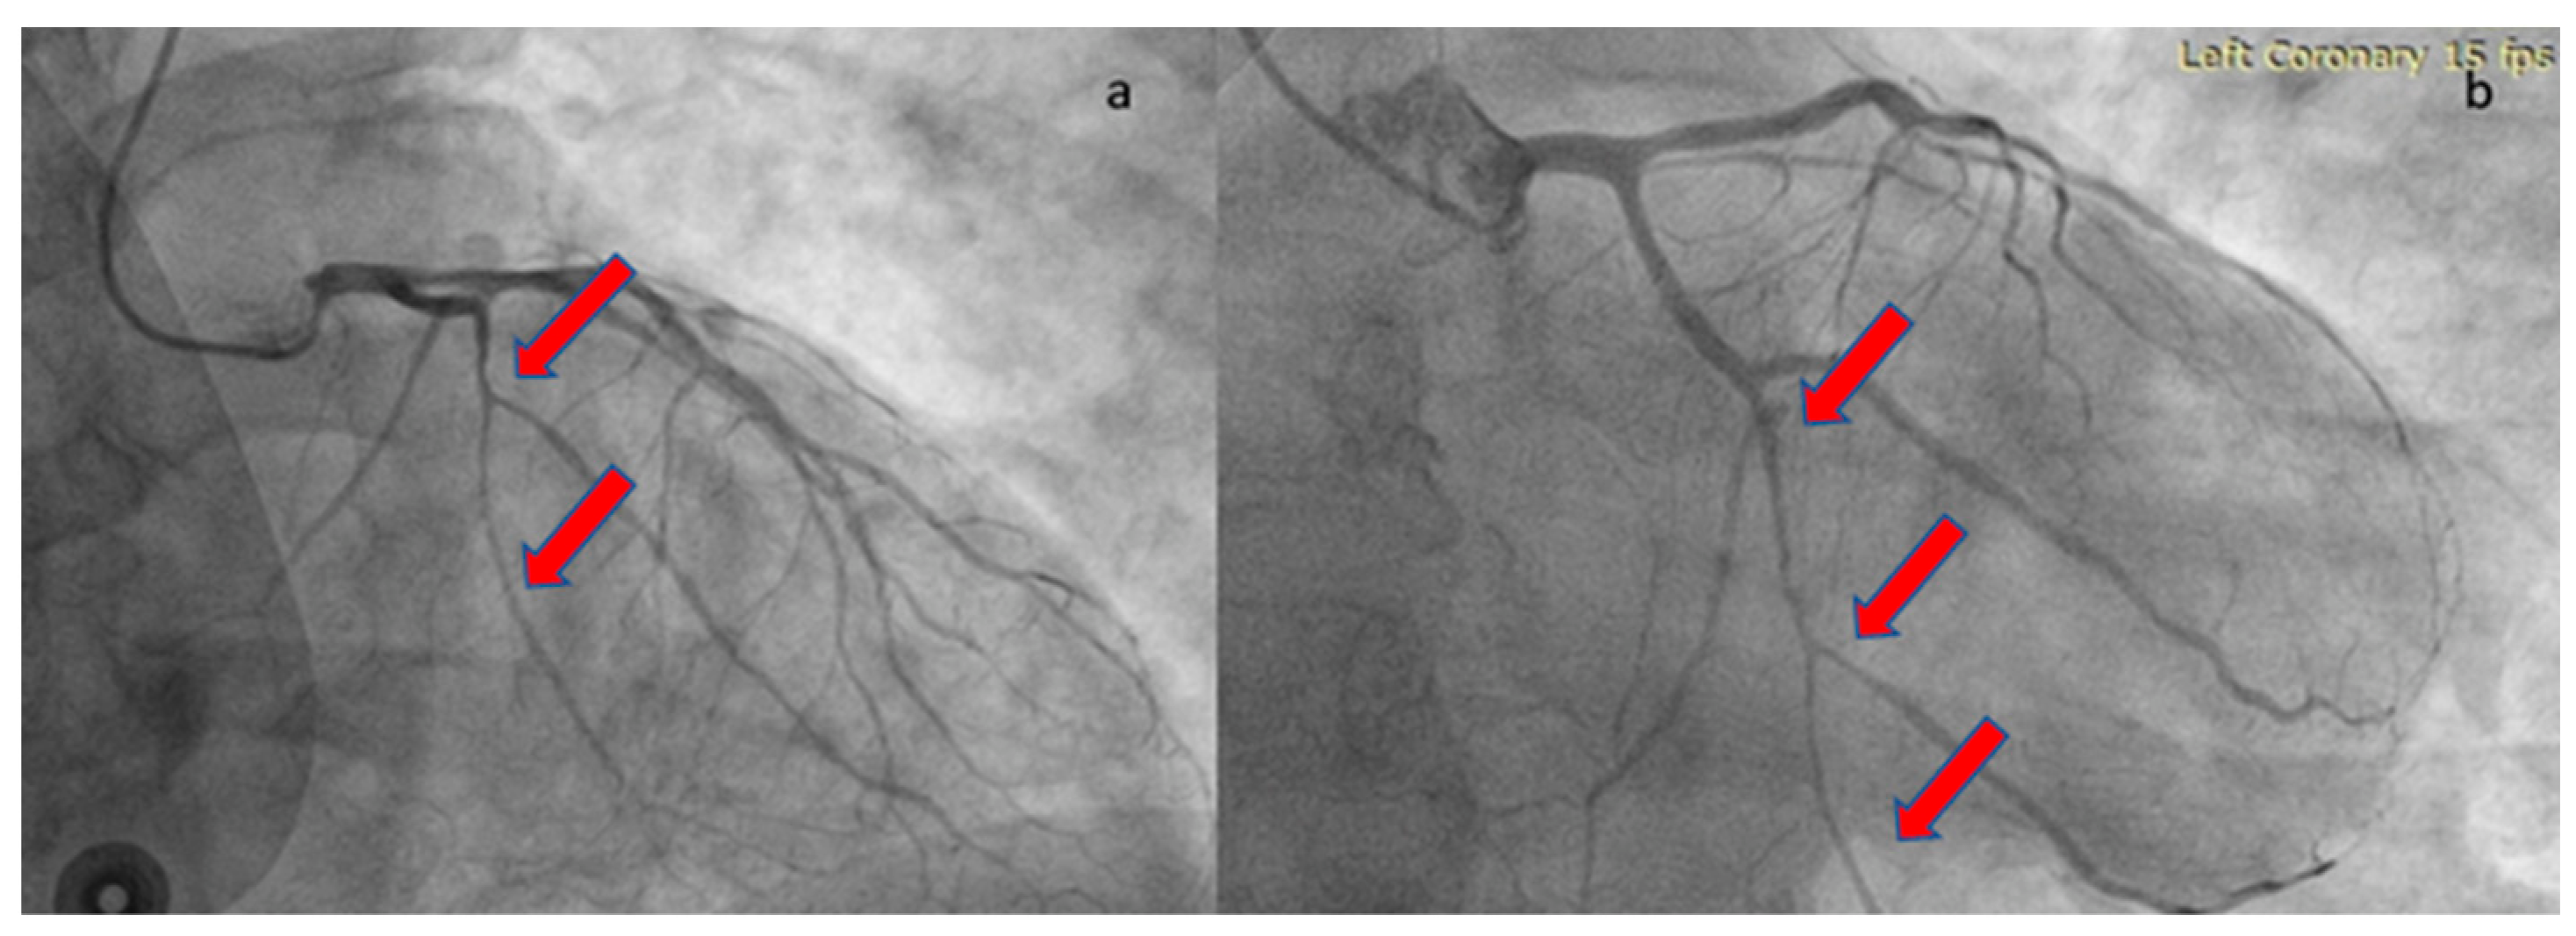

At the one-month follow-up, the patient’s health remained uncomplicated. The echocardiographic study demonstrated a full recovery of systolic function with no hypokinesia present. The repeat angiographic image was also significantly improved (Figure 4). Rivaroxaban was discontinued and the patient was advised to continue ASA for at least a year. He was also subjected to computed tomography angiography from the brain to the pelvis as part of the screening for extra-coronary arteriopathies (especially fibromuscular dysplasia), which did not reveal abnormal findings. Laboratory analyses after one month from the acute infection, including antinuclear antibodies, antibodies to β2-macroglobulin, and rheumatoid factor, were also negative, excluding the presence of chronic systemic inflammatory disease. The present case report follows the CARE case report guidelines (“see Supplementary Materials”).

Figure 4. Repeat coronary angiography of the LCX, revealing angiographic healing. The red arrows show the improvement of the previously affected vessel sections. (a) RAO cranial angiographic view; (b) RAO caudal angiographic view.